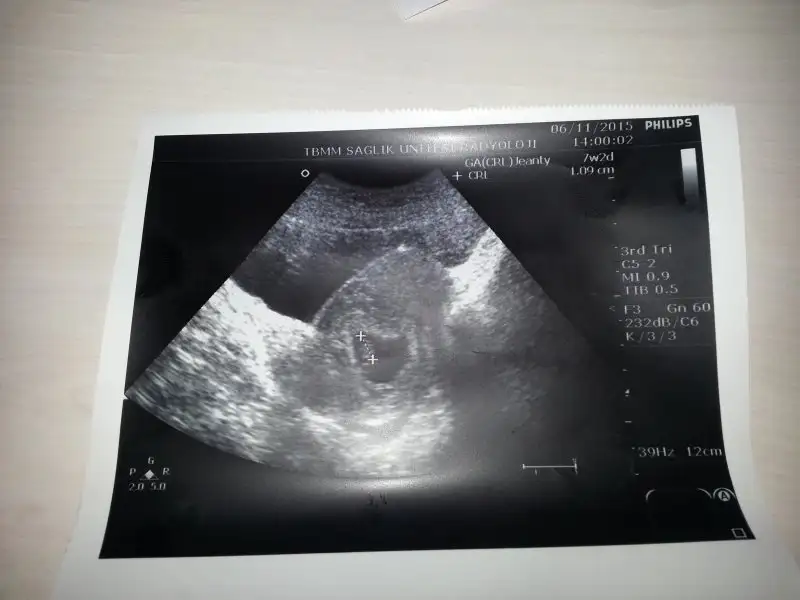

Kizlar gununuz aydin olsun insallah benim bebisime de tahmin yapabilirmisiniz kucuk ve buyuk fotosunu koydum ilk gebeligim farketmez rabbim eli ayagi duGun evlat nasip etsin hepimize

Buda son iki foto kizlar tahmininizi bekliyorum